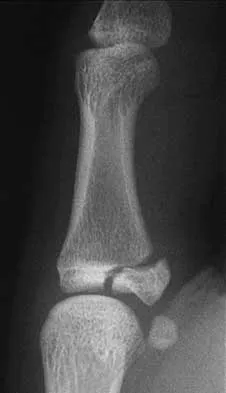

Question 10 High Yield

What is the most appropriate next step in the work-up of a patient with the asymptomatic lesion shown in Figure 23?

Detailed Explanation

The eccentric metaphyseal location, skeletal maturity, narrow zone of transition, and lack of symptoms suggest a benign process and are consistent with a healed nonossifying fibroma. These lesions typically fill in (ossify) with skeletal maturity, eventually remodeling and disappearing. Radiographic monitoring is indicated. Biopsy is not recommended unless the lesion changes radiographically. Marks KE, Bauer TW: Fibrous tumors of bone. Orthop Clin North Am 1989;20:377-393. Bullough PG, Walley J: Fibrous cortical defect and non-ossifying fibroma. Postgrad Med J 1965;41:672-676.